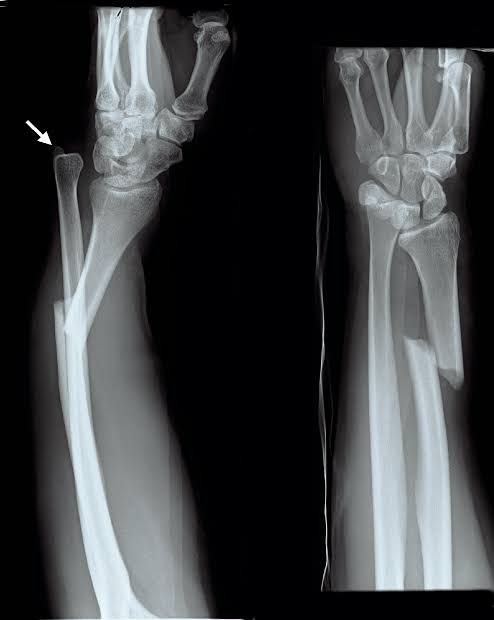

The “nightstick fracture” is a common eponym in orthopedic surgery used to describe a fracture of the ulnar shaft. The injury is termed for a fracture resulting from a defensive position when being struck with a police baton, causing an isolated fracture of the ulnar diaphysis